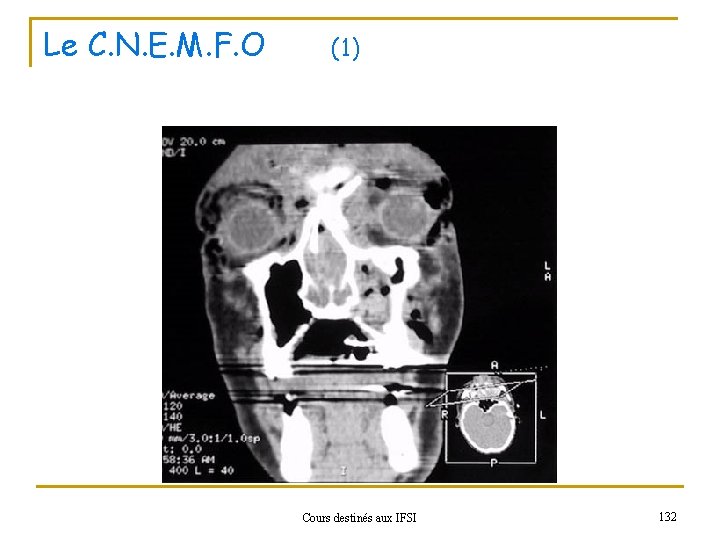

Le C. N. E. M. F. O (1) Cours destinés aux IFSI 132